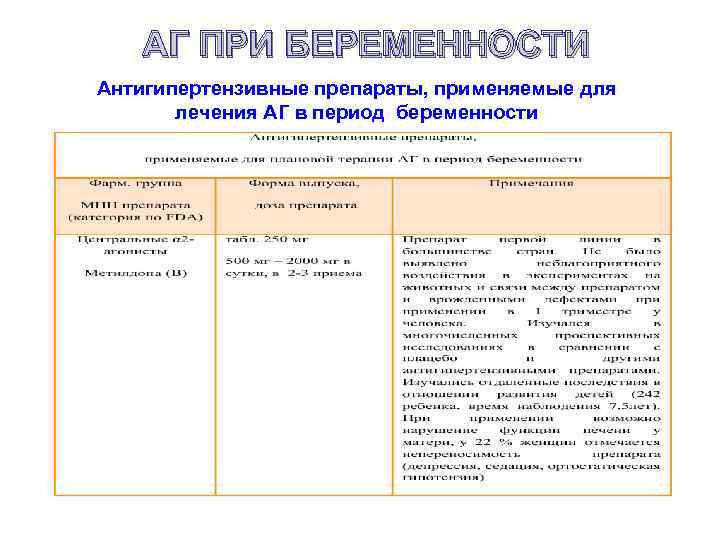

АГ ПРИ БЕРЕМЕННОСТИ Антигипертензивные препараты, применяемые для лечения АГ в период беременности

АГ ПРИ БЕРЕМЕННОСТИ Антигипертензивные препараты, применяемые для лечения АГ в период беременности